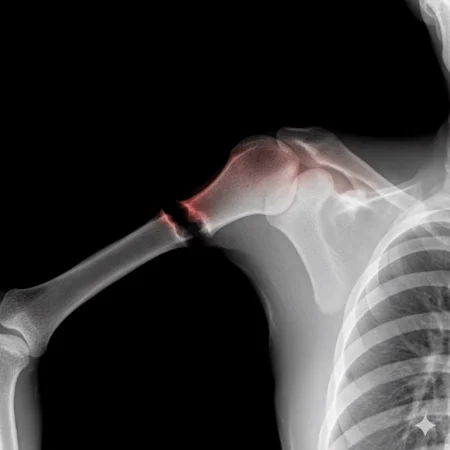

Can a model like Flux Kontext, designed for editing art and photography, be used to work with medical images, for example, with something 'as simple' as red-marking fractures?

The quick answer: it does do something interesting, but it over-scores and is far from reliable as a medical tool. It's a prototype to play with the idea, nothing more.

2. Ask: “Make marks where there is a fracture”.

AI prototypes and tests on medical imaging.

Eye-catching visualizations of "suspicious" areas in X-rays (experimental and creative art, here's an exotic tool xD)

Didactic/experimental material to play with sensitivity vs false positives.